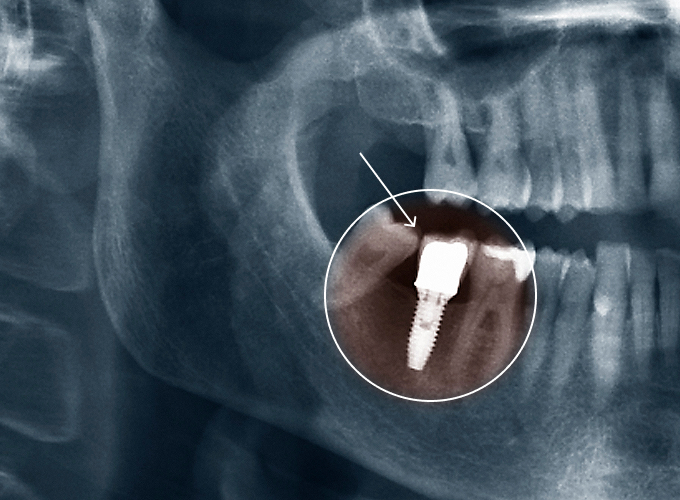

임플란트,

잃어버린 치아, 다시 찾는 자신감!

자연 치아가 빠진 자리에 인공 치아 뿌리를 심어 새 치아를 만드는 치료입니다.

틀니보다 단단하고, 진짜 치아처럼 편하게 씹을 수 있습니다.

임플란트를 위한 필요 시 시행되는 전문 치료

환자 개개인의 잇몸뼈 상태와 수술 조건에 따라, 최적의 맞춤 치료 방법을 안내드립니다.

잇몸뼈가 부족한 경우, 안정적인 임플란트 식립을 위해

뼈 보강 치료(뼈 이식술)

안정적인 임플란트를 위해 먼저 충분한 잇몸뼈를 형성한 후 임플란트를 식립하는 술식입니다. 잇몸뼈가 부족한 경우에는 안전한 재료를 사용해 부족한 뼈를 보충한 뒤, 임플란트를 안전하게 심을 수 있도록 합니다.